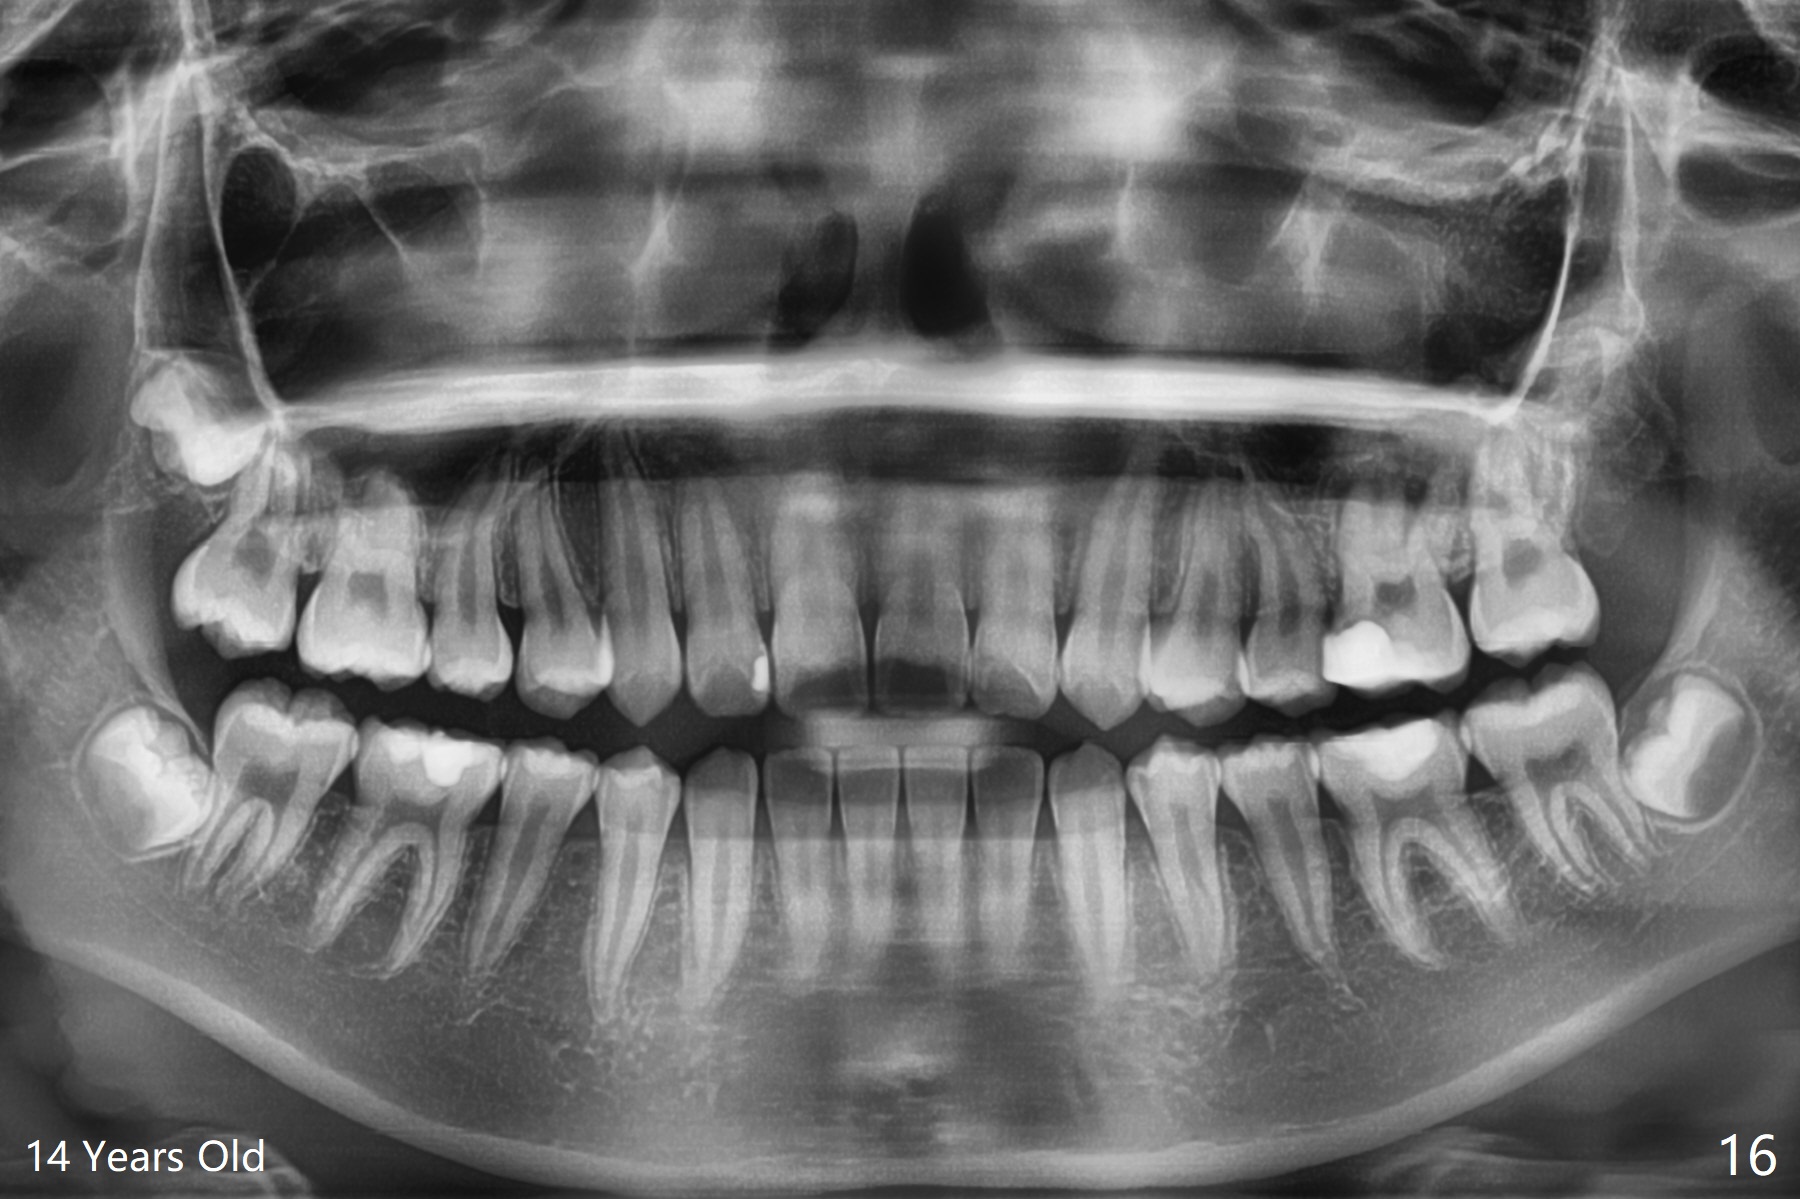

A 14-year-old woman, used to be a dental phobic (Fig.13), agrees with orthodontic treatment. Her mother is concerned about UL1 protrusion (Fig.8,11) and decalcification (Fig.8 *) and UR4 cross bite (Fig.7,10,14). There is mild lip constraint (Fig.1,3), as related to light dental protrusion (Fig.2,4), although the upper dental midline is not deviated (Fig.2). History shows that UR3 erupts before UR D is extracted, which is associated with UR4 cross bite. After arch expansion, consider proximal reduction to reduce anterior overjet if present. In fact that latter is not done; instead Class II is conducted.